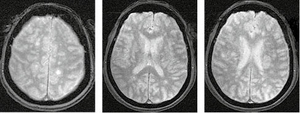

У режимі Т2*/T2 GRE на МРТ-зображенні головного мозку пацієнта з ГРЕМ візуалізуються двобічні гіперінтенсивні вогнища без геморагічного компоненту, що є типовою ознакою ГРЕМ, на відміну від гострого геморагічного лейкоенцефаліту (хвороби Херста) (рис. 3).

/images/nn257-1622023r3_.jpg)

На рисунку 4 наведено МРТ-зображення головного мозку пацієнта з гострим геморагічним лейкоенцефалітом (хворобою Херста) у режимі Т2*/T2 GRE, де візуалізуються двобічні гіперінтенсивні вогнища, два з яких містять геморагічний компонент, та в режимі Т2. А на рисунку 5 — МРТ-зображення головного мозку пацієнта з ГРЕМ у режимі Т2 — продемонстровано важливу ознаку ГРЕМ (на відміну від РС): відносну інтактність мозолистого тіла, стовбура мозку, середніх мозочкових ніжок та мозочка, які в разі РС, як правило, уражаються першочергово. Вказана ознака не завжди є показовою, але має високу інформативність для диференційної діагностики.

/images/nn257-1622023r4_.jpg)

/images/nn257-1622023r5_.jpg)